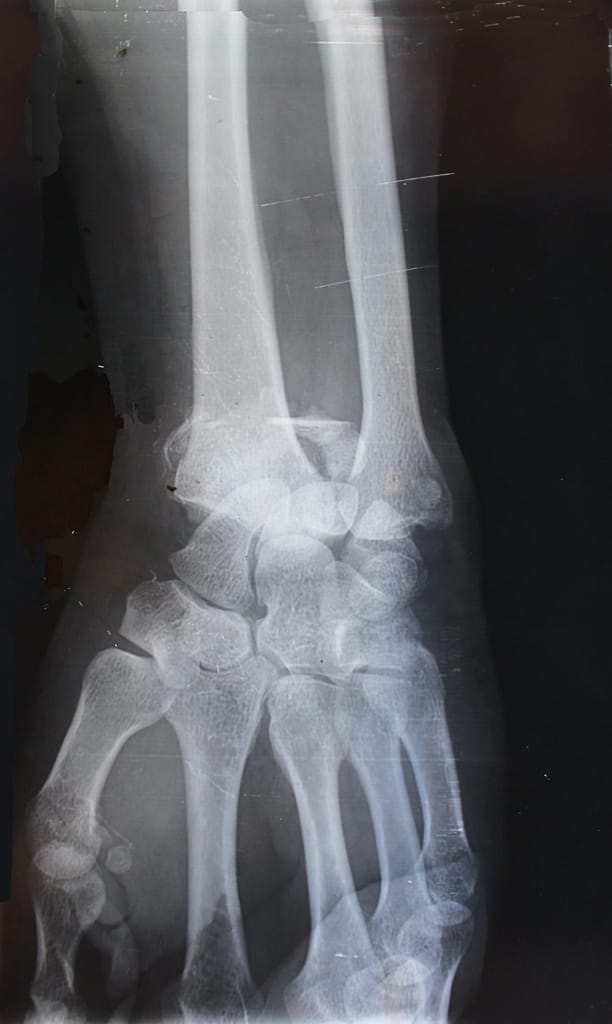

Photon counting X-ray imaging is a revolutionary technology, the highlight in a history of remarkable advances in X-ray imaging that began with Röntgen’s unforgettable first image of the delicate, skeletal structure of a hand. Varex Imaging is at the forefront of this technology.

Photon counting detectors measure the energy of individual photons after they have passed through the patient’s body. Every X-ray creates an electric signal in the detector material which corresponds to the energy of the photon. This signal is analyzed and based on its strength, it is separately recorded into the corresponding energy channel of the correct pixel. This energy discrimination is intrinsic to the technology and doesn’t require additional system components or added radiation dose.

The benefits include better spatial resolution, improved contrast – in many applications – lower radiation dose. Photon counting also enables the separating tissues, or combined, to form ‘color’ images – after the acquisition. The added energy domain information allows sophisticated post-processing algorithms which can aid the user to focus on the areas of clinical interest.